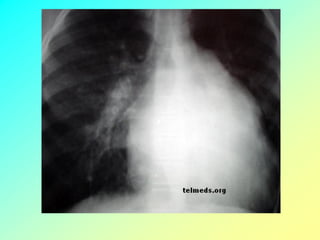

INSUFICIÊNCIA RESPIRATÓRIA DISTRIBUTIVA

e drenagem deficiênte

EDEMA AGUDO DE PULMÃO

Na IM AGuda (como ocorre no IAM ou na ruptura de cordoalha) há

sobrecarga volumétrica intensa e súbita, sem tempo suficiente para AE e VE se

adaptarem – AE pequeno e não complacente transmite toda a sobrecarga pressórica

da IM aguda para o leito vascular pulmonar – congestão e hipertensão pulmonar

(EAP) – redução do débito cardíaco (DC) – choque cardiogênico.

O incremento dessas pressões sem adaptação do átrio , levam ao aumento

da PCP, podendo levar em situações específicas ao EAP.